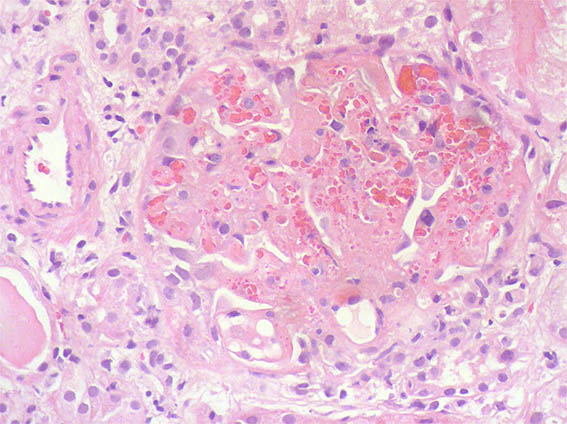

A 25-year-old woman with no relevant history is evaluated for presenting 3 months of evolution of constitutional symptoms, disseminated skin lesions with vasculitis-like appearance, polyarthritis affecting small and medium joints, anemia, acute phase reactants elevation, lymphopenia, hypocomplementemia C3 and C4, uroanalysis with active sediment and subnephrotic proteinuria: 1.8 g/24h; Cr; 1.1 mg/dL, BUN: 18 mg/dL. ANAs and anti-DNA positive at high titers, anti-RNP positive, VDRL falsely positive. Anticardiolipin and lupus anticoagulant: negative, other markers for APS: Negative.

See the images of the renal biopsy.

Figure 1. H&E, X100.

Figure 2. H&E, X400.

Figure 3. PAS, X400.

igure 4. H&E, X400.

Figure 5. Methenamine-silver, X400.

Figure 6. H&E, X400.

Figure 7. H&E, X400.

What lesion is evidenced in figures 6, 7 and 8 and what is its etiology?